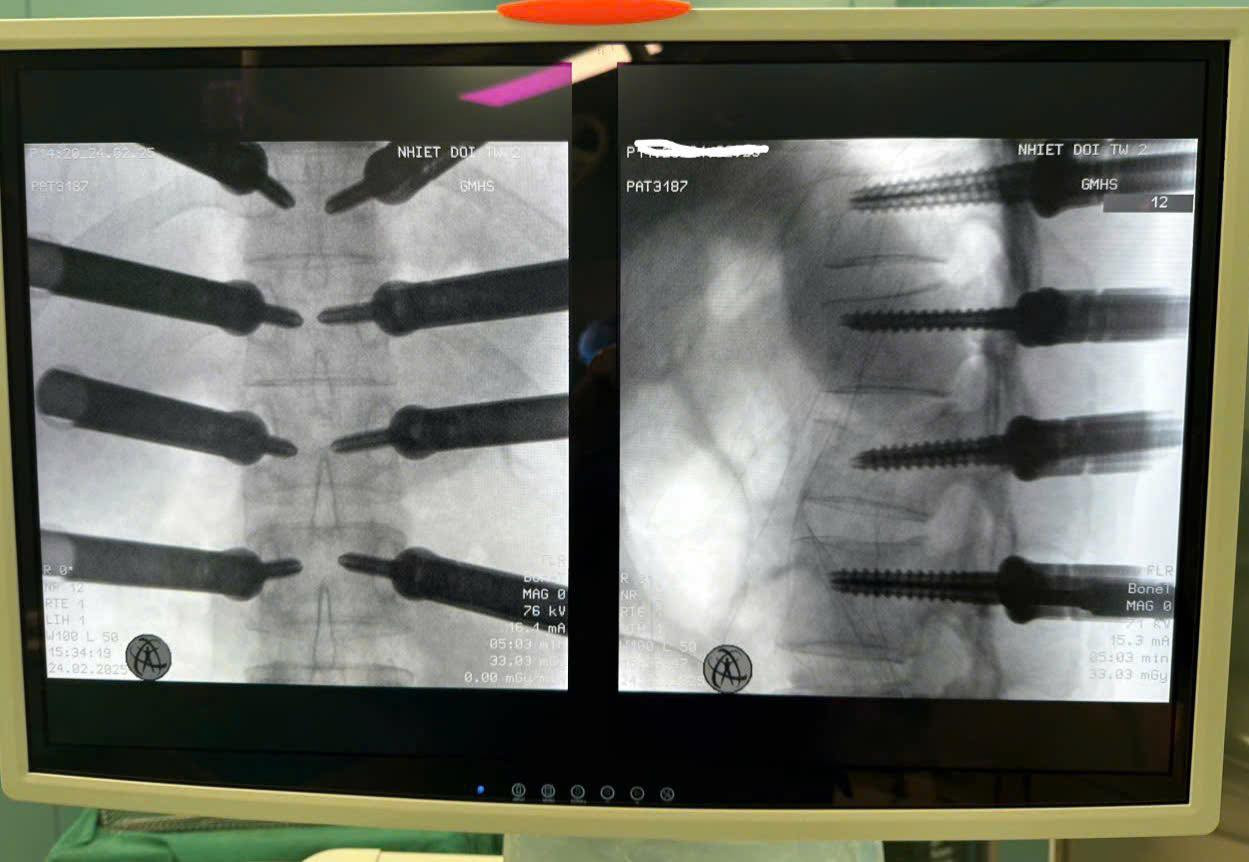

![]() |

| Hình ảnh cột sống đã được bắt vít. Ảnh: Bệnh viện cung cấp |

Theo bác sĩ Tùng, nhờ sự hỗ trợ của công nghệ hiện đại trong suốt quá trình mổ như máy chụp Xquang phòng mổ, hệ thống định vị C-arm giúp các bác sĩ xác định vị trí vít chính xác, nâng cao hiệu quả điều trị và giảm thiểu rủi ro.